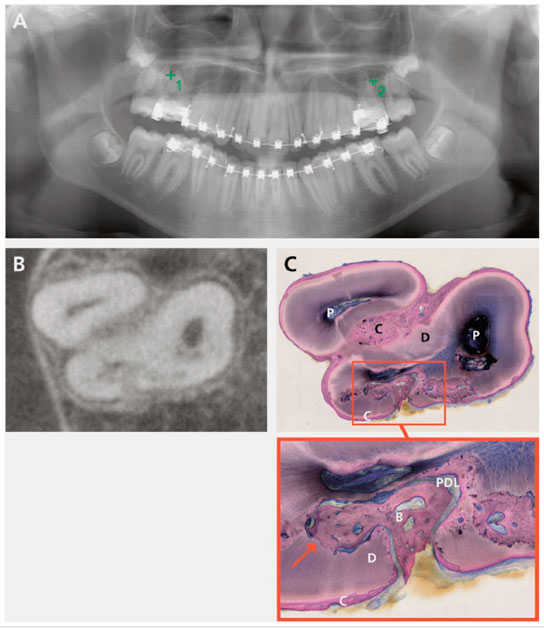

Figura 1: Sospecha de anquilosis del diente 16 y 26 en el PV (A) (solo 16 estaba histológicamente disponible).

Signos claros de anquilosis en CBCT (B) y en corte histológico correspondiente (C).

La anquilosis se ve claramente como una fusión del hueso con la dentina (flecha).

B, hueso; C, cemento; D, dentina; P, pulpa; PDL, ligamento periodontal

Para lo cual se recogieron una serie de dientes clínicamente diagnosticados como anquilosados ​​después de su extracción en una práctica privada de 2009 a 2015 y analizada retrospectivamente. Los criterios de inclusión fueron que sean molares permanentes extraídos debido a erupción dental fallida en ausencia de cualquier obstrucción mecánica visible, que tengan una radiografía panorámica existente (PV), tomografía computarizada con haz de cónico (CBCT) y secciones histológicas del diente. Los escaneos CBCT y los PV se evaluaron dos veces por signos de anquilosis por dos observadores especializados y de manera independiente usando la siguiente puntuación: signos claros, posibles y con ausencia de signos. (Figura 1)